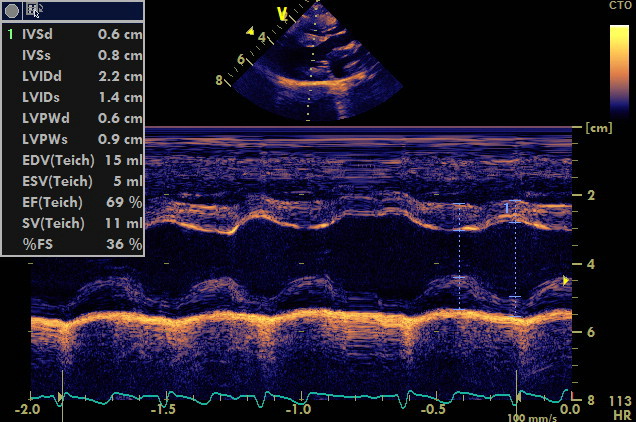

Questo e’ un caso classico che coinvolge la porzione perimembranosa ,la gravita’ del difetto e’ ovviamente proporzionale alla sua ampiezza ,in questo caso il difetto non supera i due millimetri i gradienti tra ventricolo sx e destro sono stimati dal doppler nella norma ,emodinamicamente non dovrebbe comportare lo sviluppo di sovraccarichi significativi del cuore sx . Diversamente i difetti piu’ ampi generano inevitabilmente overcirculation (per lo shunt sx destro emodidamicamente significativo) e sviluppo di scompenso cardiaco sx ,in alcuni casi oltre i due anni l’arteriopatia progressiva generata dall’overcirculation puo’ innalzare la pressione in polmonare e invertire lo shunt.

gradiente transventricolare di 178 mmHg questo e’ un pattern restrittivo compatibile con basse pressioni nel cuore di destra da considerare un bene per il soggetto ,gradienti minori indicano innalzamento delle pressioni nel ventricolo destro .

nessuna evidenza di ingrandimento ventricolare